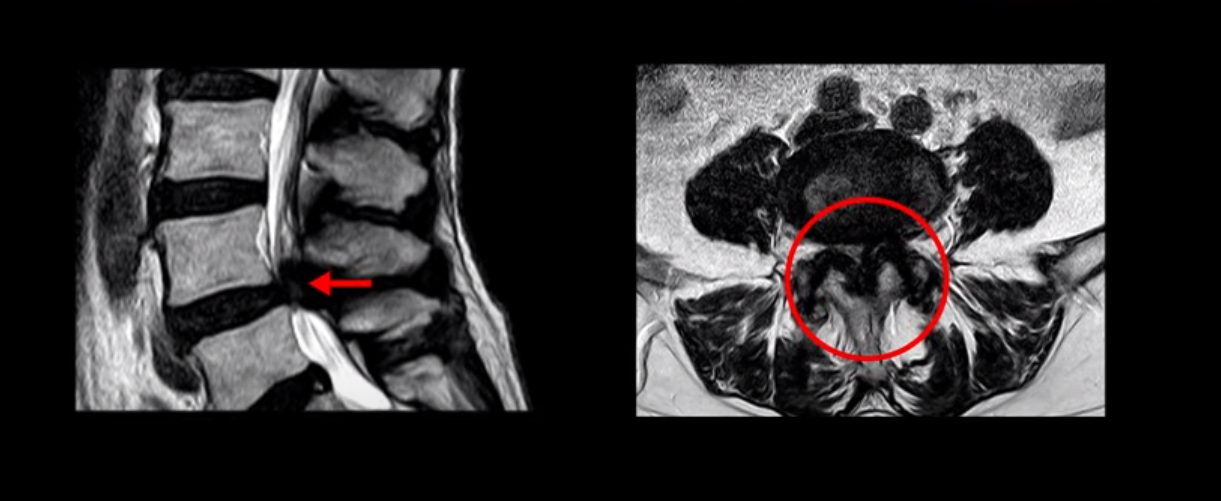

이분 MRI를 보면 허리 여러 마디가 퇴행되어 있고 여러 군데 협착이 있는데

특히 4번 5번 마디의 척추관협착 즉, 중심성 협착은 너무나도 심해 보입니다.

아예 신경이 거의 보이지 않을 정도입니다. 이 정도로 협착이 심하니까 수술 밖에는 방법이 없다고 얘기를 듣고 증상도 매우 심합니다. 양쪽 엉덩이부터 다리 발바닥까지 아프고 다리의 감각이 떨어지고 시린 증상이 있습니다. 걸을 때 마비가 오면 슬리퍼가 벗겨져도 모른다고 하셨고 잠도 제대로 못 자는 상태였습니다. 그런데 이렇게 협착이 심해 보이고 증상도 심한 환자분을 어떻게 수술 없이 치료 가능한 걸까요? 지금부터 설명해 드립니다.